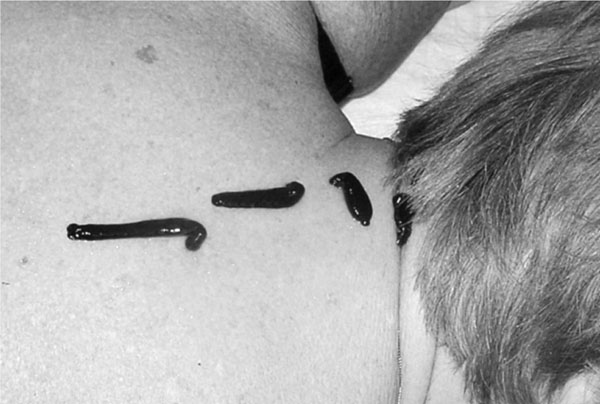

Постановка пиявки пациенту на копчик и крестец

Пятая постановка – крестец и копчик. Зона копчика – важнейшая зона. Этот отдел позвоночника служит для прикрепления мышц и связок, благодаря которым функционируют органы мочеполовой системы, толстый кишечник. А изменение тонуса мышц, связок, самого копчико-крестцового сочленения приводит к изменению положения внутренних органов малого таза – это мочевой пузырь, матка и ее придатки, предстательная железа, прямая кишка. Без проработки этой зоны даже не надейтесь привести в порядок гинекологию и урологию. На анатомическом уровне тоже все взаимосвязано: мозг человека имеет участки коры, которые координируют и управляют функциями и работой каждого органа или системы в интересах всего организма в целом. Каждая зона коры генерирует свои нервные сигналы для этого управления. Именно позвоночник «доставляет» эти сигналы, и копчик является важным звеном, без которого «связи» между гипофизом – гипоталамусом и органами человека – не будет. К тому же, согласно восточным практикам, это зона сгустка энергии кундалини (находится в треугольной крестцовой косточке). Когда энергия кундалини при пробуждении поднимается, тогда в сознании и в теле человека начинается новый жизненный процесс.

Интересно, что те из моих пациентов, которые получили травму копчика, даже в детстве, болели чаще и имели проблемы в области малого таза. Константин Васильевич Сухов, руководитель Московского центра подготовки гирудотерапевтов, неоднократно в течение первого курса практикует постановки на копчик. Если не было травм копчика, я ограничиваюсь одной-двумя постановками в эту зону, так как в ней обычно длительное кровотечение и кровь потихоньку стекает между ягодиц, доставляя некоторые неудобства пациенту. Однако я усиливаю эту постановку еще тремя-четырьмя пиявками в зону крестца и поясницы, где обычно бывают явления радикулита и остеохондроза. Эта зона относится и к ногам – она обязательна при проблемах с суставами и венами ног. Итак, ставим шприцем одну пиявочку на «хвостик», по одной – в ямочки на крестце и одну – две на поясницу.